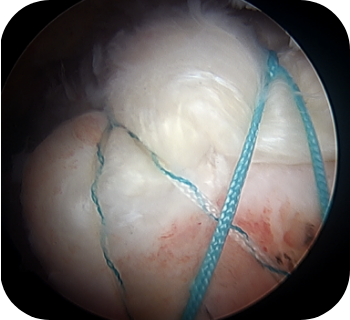

파열 범위가 큰 광범위 파열인 경우, 가능하면 일차 봉합술을 시행하는 것이 바람직하나, 내측으로 말려들어간 힘줄을 무리하게 당겨 봉합을 할 경우 재파열이 빈번하게 일어날 수 있습니다. 우선 관절경으로 견봉 성형 및 점액낭을 제거한 후 파열의 정도와 모양을 확인하고, 복원 불가능한 파열에서는 부분 복원술을 시행한 이후 피부조직이식술을 시행하게 되는데, 이는 노출된 상완 골두를 덮어주고 봉합한 힘줄을 보강시켜줄 수 있는 방법입니다.

▲ 회전근개 봉합술 후